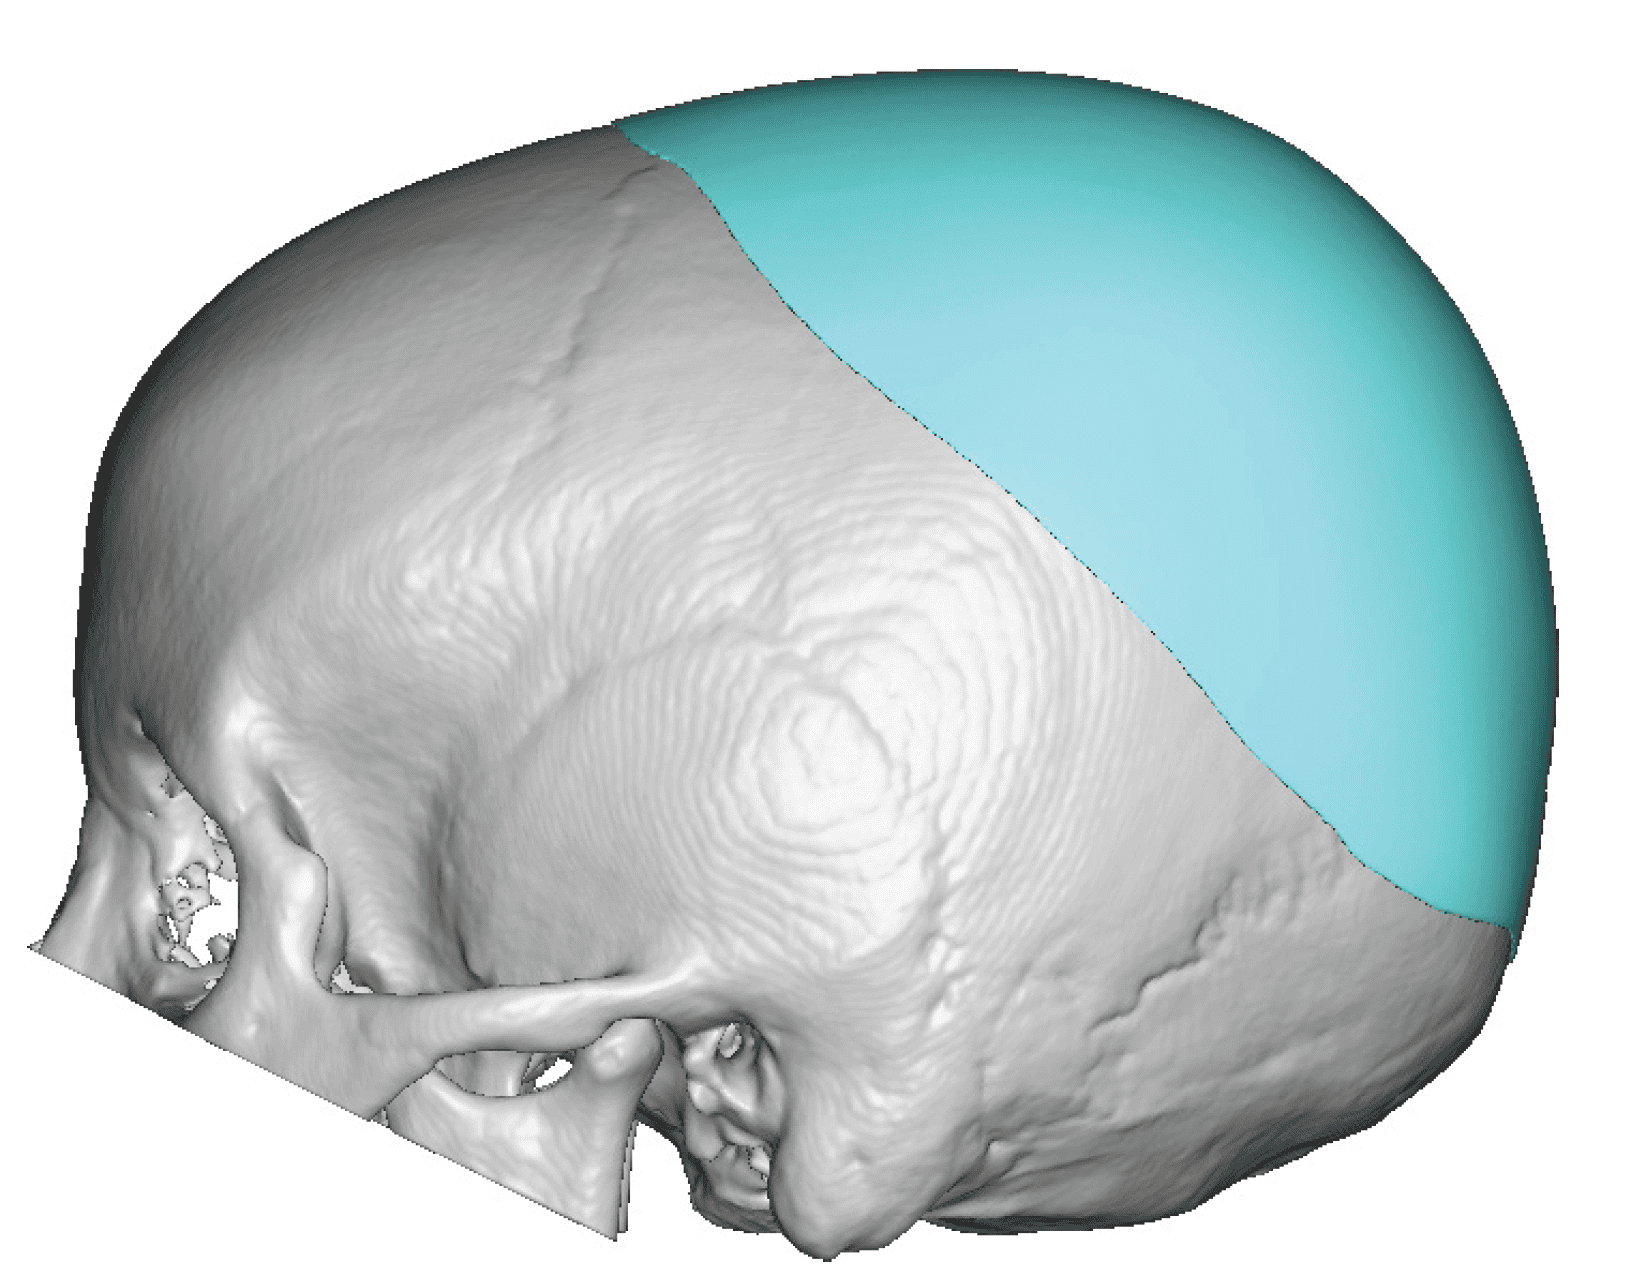

Desire for increased projection of flat back of head.

Placement of a custom skull implant to increase the projection of the back of the head by 15mms and 120ccs of volume.